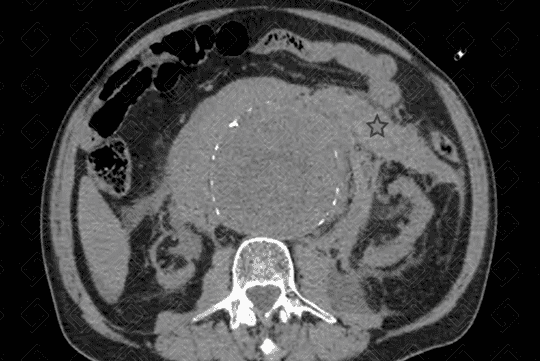

Texto alternativo para a imagem Figura 1. Créditos: Dra. Elazir Mota - Rio de Janeiro/RJ

Descrição das figuras 1, 2 e 3: Sinais de ruptura de aneurisma da aorta abdominal com extenso hemoperitônio. Hematoma hiperdenso mais bem apreciado nas fases sem contraste (asteriscos - figuras 1 e 2), que se estende ao espaço pararrenal e perirrenal esquerdo. Após a administração do contraste, observa-se extravasamento ativo do mesmo (seta vermelha - figura 3). [cms-watermark]

Complicações: Como complicações do aneurisma, as principais são ruptura (figura 1) e fístula do aneurisma para órgãos vizinhos (rara).